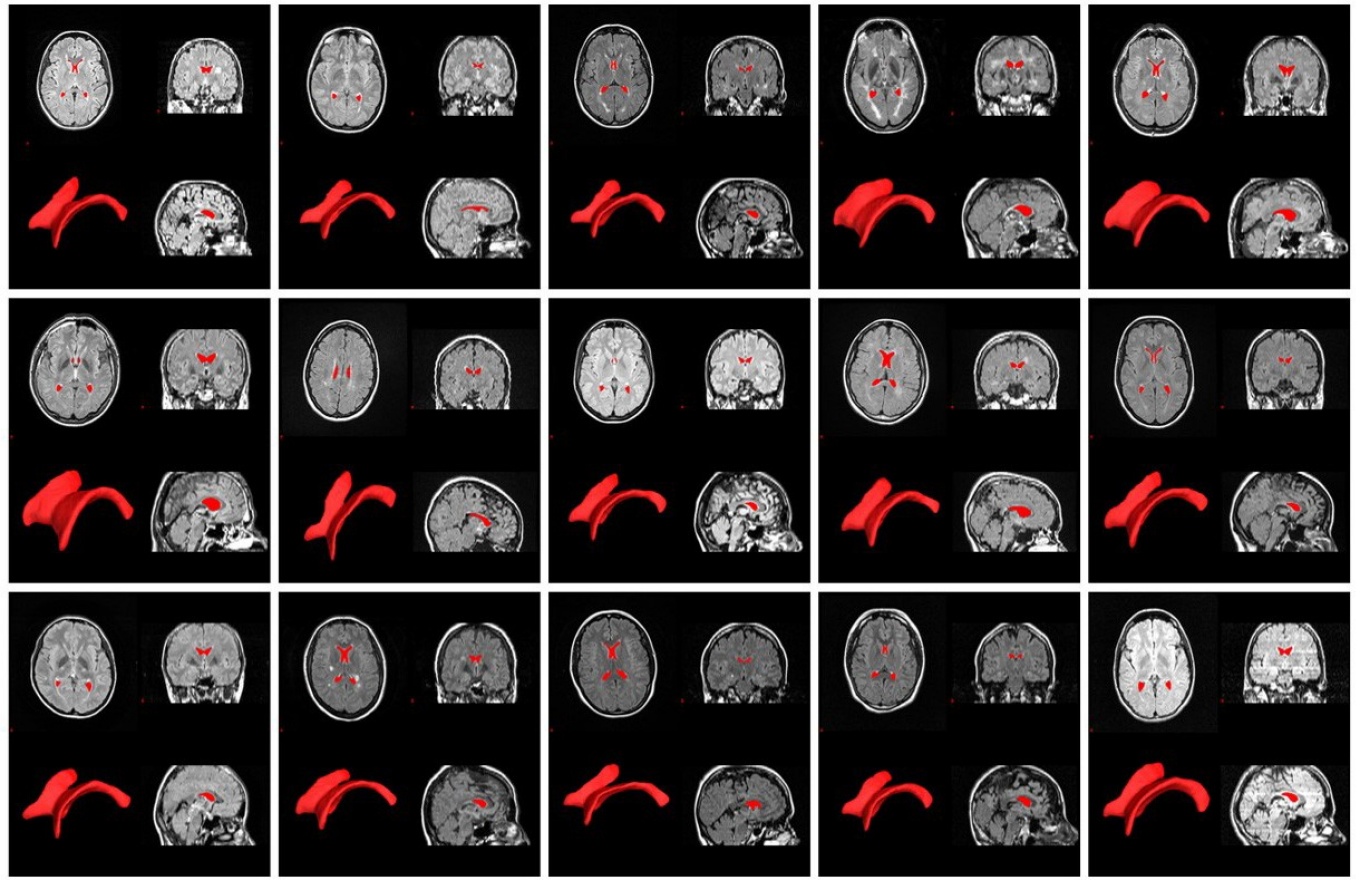

Zivadinov explains that the top research area for investigators using these machines is neurodegenerative disorders, such as Alzheimer’s disease, Parkinson’s disease, multiple sclerosis, epilepsy, systemic lupus erythematosus and stroke. The second area is the study of concussion or traumatic brain injuries (TBI), an area in which UB investigators have made significant advancements. The third is heart disorders.

Imaging makes important contributions to translational research via testing of new diagnostic and therapeutic interventions. For example, as part of a CTSI-funded pilot study, Ferdinand Schweser and David Poulsen have identified via MRI early changes following traumatic brain injury in a preclinical model of concussion. This observation holds promise for significant advancement in the diagnosis and management of traumatic brain injuries and post-concussion syndrome in patients.